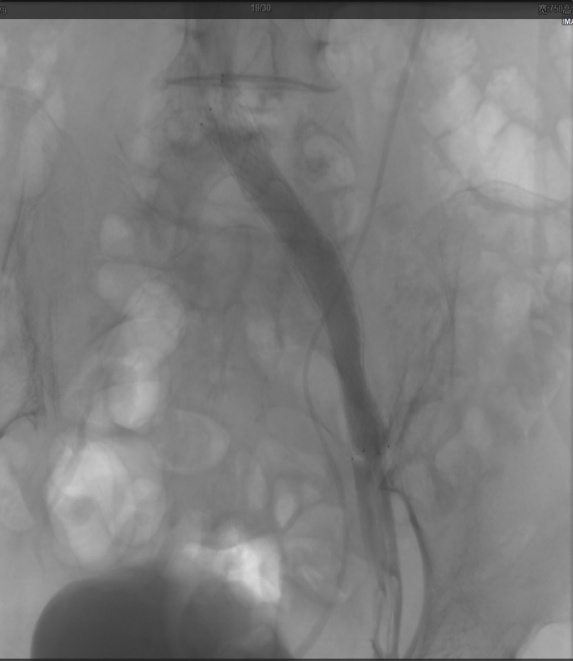

术后DSA造影:左侧髂静脉显示良好。